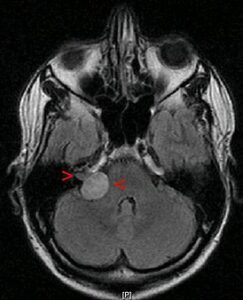

Новообразование, имеющее доброкачественную форму, способно вызывать осложнения, сдавливая окружающие структуры и ткани. Невриномы, сформированные из нервных клеток, образуются в вестибулярном корешке слухового нерва, и представляет собой бугристый или округлый узел плотной консистенции, состоящий из кистозных элементов, заполненных жидкостью. Опухоль характеризуется медленным ростом и не выходит за пределы очага, не распространяется на здоровую ткань. Но вырастая до больших размеров, шваннома постепенно негативно влияет на слух, оказывает давление на соседние структуры, ухудшая качество жизни. Появление образования связывают с наследственной предрасположенностью и генетическим заболеванием. Невринома может быть односторонней или двусторонней и квалифицируется по стадиям развития, что зависит от размеров образования.